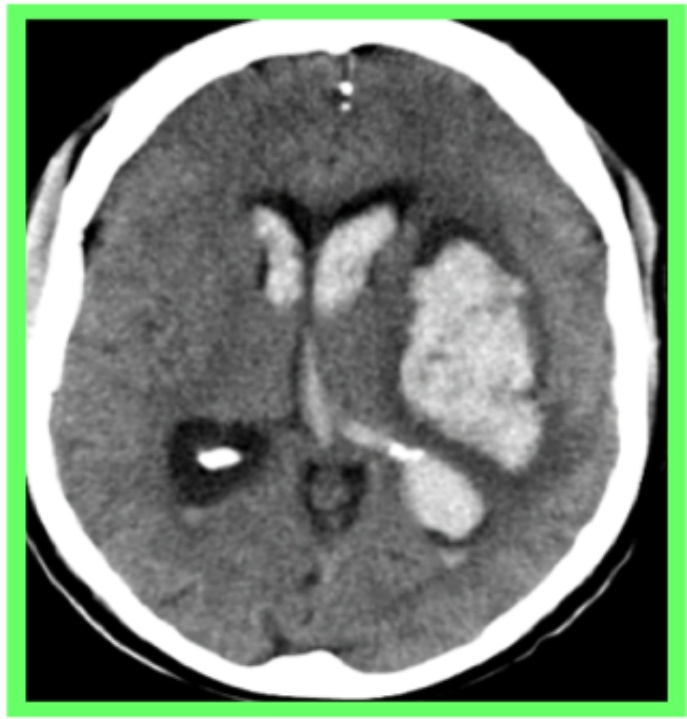

Ischemic stroke was predominant, accounting for 83.3% represented by Figure 1 of cases, consisting mainly of lacunar infarcts and established ischemic strokes, most often located in the superficial or deep Sylvian territory represented by Figure 2. Haemorrhagic lesions accounted for 16.7% and were often distributed as capsulolenticular and capsulothalamic haematomas. Shown in Table 2.

Figure 1. Right capsulolenticular hypodensity in the deep Sylvian territory consistent with ischaemic stroke.

On CT scans, Sylvian lacunar ischaemic strokes predominated, which was practically similar to the results observed in Côte d’Ivoire [11]. Haemorrhagic strokes consisted mainly of intraparenchymal haematomas, preferentially located in the capsulo-lenticular or capsulo-thalamic regions.

Strokes remain a daily concern in the Central African Republic, as in other African countries. In this study, computed tomography improved the diagnosis of strokes, enabling a better distinction between ischaemic and haemorrhagic strokes and identifying the topography of the lesions. The vast majority of these strokes were ischaemic in nature, occurring in the superficial or deep Sylvius territory. Haemorrhagic lesions were dominated by intraparenchymal haematomas, preferentially capsulo-lenticular or capsulo-thalamic.